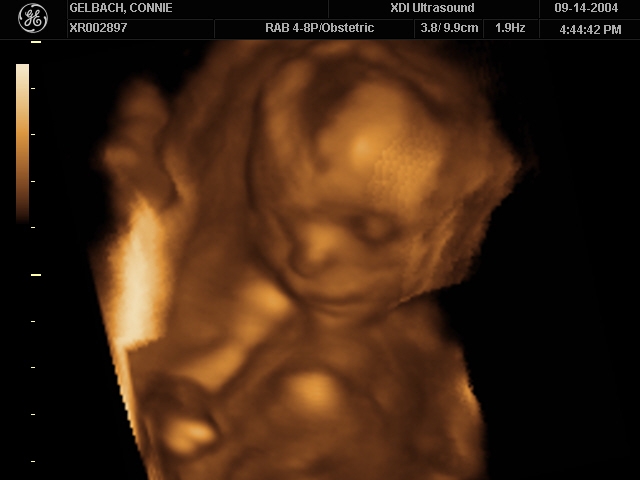

Sonograms